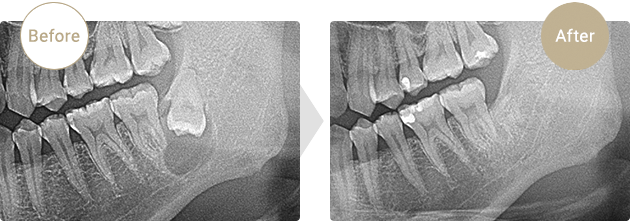

症例.02

歯原性嚢胞

50歳代男性。左下の親知らずが原因と思われる嚢胞を歯を含め摘出しました。その後、術後の麻痺や再発もなく骨の増生が認められます。